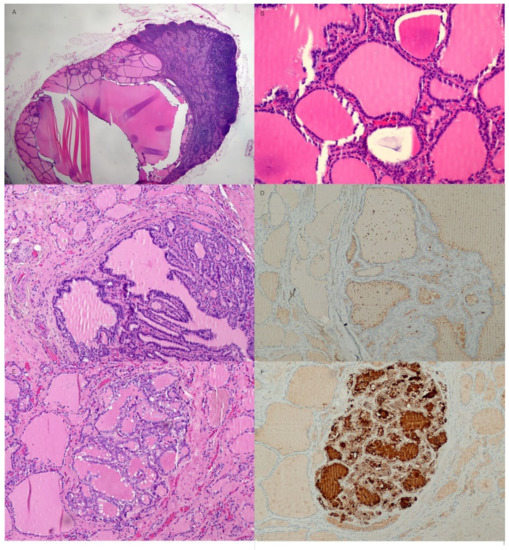

Histologic features of the cervical lymph nodes and thyroid gland. (A) A cervical lymph node is replaced by benign thyroid tissue with cystic change (hematoxylin and eosin stain (H&E), X20). (B) Numerous thyroid follicles containing pink colloid material are tightly packed (H&E, X200). (C) Both lobes of the thyroid gland have multiple follicular nodules showing mild nuclear enlargement and irregularity but no definite evidence of nuclear grooves or intranuclear inclusions indicating papillary thyroid carcinoma (H&E, X100). (D) The immunohistochemical stain for HBME-1 shows a negative reaction in the adenomatous nodule of the thyroid (HBME-1, X100). (E) A well-demarcated, 2 mm sized, atypical nodule composed of irregular nuclei with a ground-glass appearance in the remnant left lobe of the thyroid (H&E, X100). (F) Strong positive HBME-1 staining in the follicular cytoplasms of an atypical thyroid nodule was seen (HBME-1, X100). Additionally, real-time PCR for BRAF V600E mutation did not detect BRAF V600E mutations in any of the nodules of the thyroid and cervical lymph nodes. In case of cervical lymphadenopathy, it is necessary to differentiate between lymph node metastasis of occult thyroid carcinoma and that of benign intranodal thyroid tissue. The probability of clinically detecting occult thyroid carcinoma by autopsy in cervical lymph nodes is over 25% [12]. In addition, the probability of occult thyroid carcinoma metastasizing to the cervical lymph node is 0.7% [13]. For patients who have undergone cervical lymphadenectomy, the probability of having benign thyroid inclusions or psammoma bodies is 0.8%, and the probability of having benign intranodal thyroid tissue in the head and neck lymph nodes based on autopsy or neck dissection is 0.6 to 5.0% [13,14]. Therefore, benign intranodal thyroid tissue can have a false-positive result of metastasis of occult thyroid carcinoma in the cervical lymph node, therefore, a careful approach is needed for preoperative discrimination. In the US, the probability of malignancy is 74.3% in cases of diffusely increased echogenicity, whereas the probability of malignancy is not low at 43.8% for focally increased intranodal echogenic islands. In addition, when features such as intranodal calcification, intranodal cystic changes, and abnormal vascular patterns are observed, lymph node metastasis of papillary thyroid carcinoma can be suspected [14,15]. Additionally, on the cervical CT scan, when strong or heterogenous enhancement, intranodal calcification, or cystic change is observed, malignancy is suspected [14,16]. In addition to the typical nuclear features of papillary thyroid carcinoma with intranuclear grooves, intranuclear inclusion bodies and a ground-glass appearance, immunohistochemical staining, especially HBME-1, is helpful in distinguishing between intranodal benign thyroid tissue and metastatic papillary carcinoma in the lymph nodes [9]. Additionally, real-time PCR for BRAF V600E mutation test can be performed to further enhance the accuracy of the diagnosis. There are several hypotheses regarding the origin of benign intranodal thyroid tissue. It is believed to be due to abnormal migration of benign tissue during embryogenesis, neoplastic transformation of the remaining cells, or metastatic spread of a clinically silent malignancy [14]. In this case, considering that the patient had benign thyroid tissue in the cervical lymph nodes ranging from level II to level VI, the benign thyroid tissue appeared to be embedded in the chain of cervical lymph nodes because the benign thyroid tissue was adherent to the surrounding tissue from previous thyroid surgery and deep cervical inflammation. In the embedded benign thyroid tissue of cervical lymph nodes, cystic changes were commonly observed. In conclusion, benign thyroid tissue could be included in many lymph nodes along the cervical lymph node chain because of adhesions from previous thyroid surgery and deep cervical inflammation. Benign intranodal thyroid tissues may enlarge with cystic changes. Therefore, it is necessary to differentiate it from metastatic lymph nodes of thyroid papillary carcinoma. Immunohistochemical staining for HBME-1 and real-time PCR for the BRAF V600E mutation, in addition to histologic examination, are also helpful.